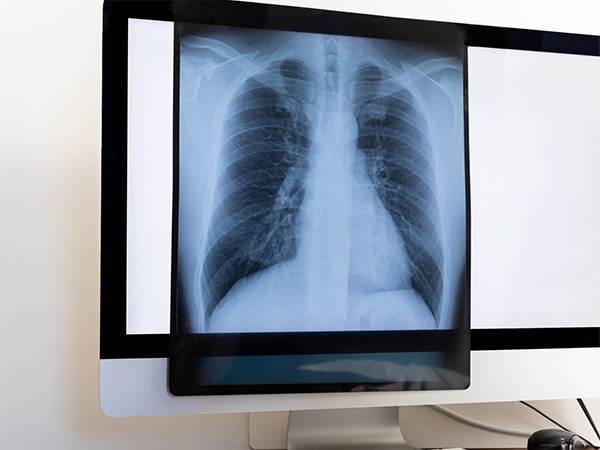

TRAFFIC ACCIDENT交通事故・労災

当院では、交通事故による外傷の検査(レントゲン、MRI等)・治療を行っています。

支払いに関しての各保険会社との対応もできます。

また仕事中の外傷(労災・公務災害等)の治療も承っています。